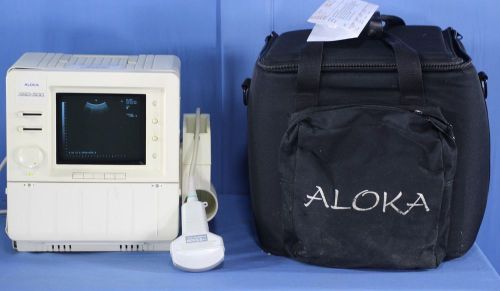

Aloka SSD-500 Portable Ultrasound - can be used for Veterinary with Warranty